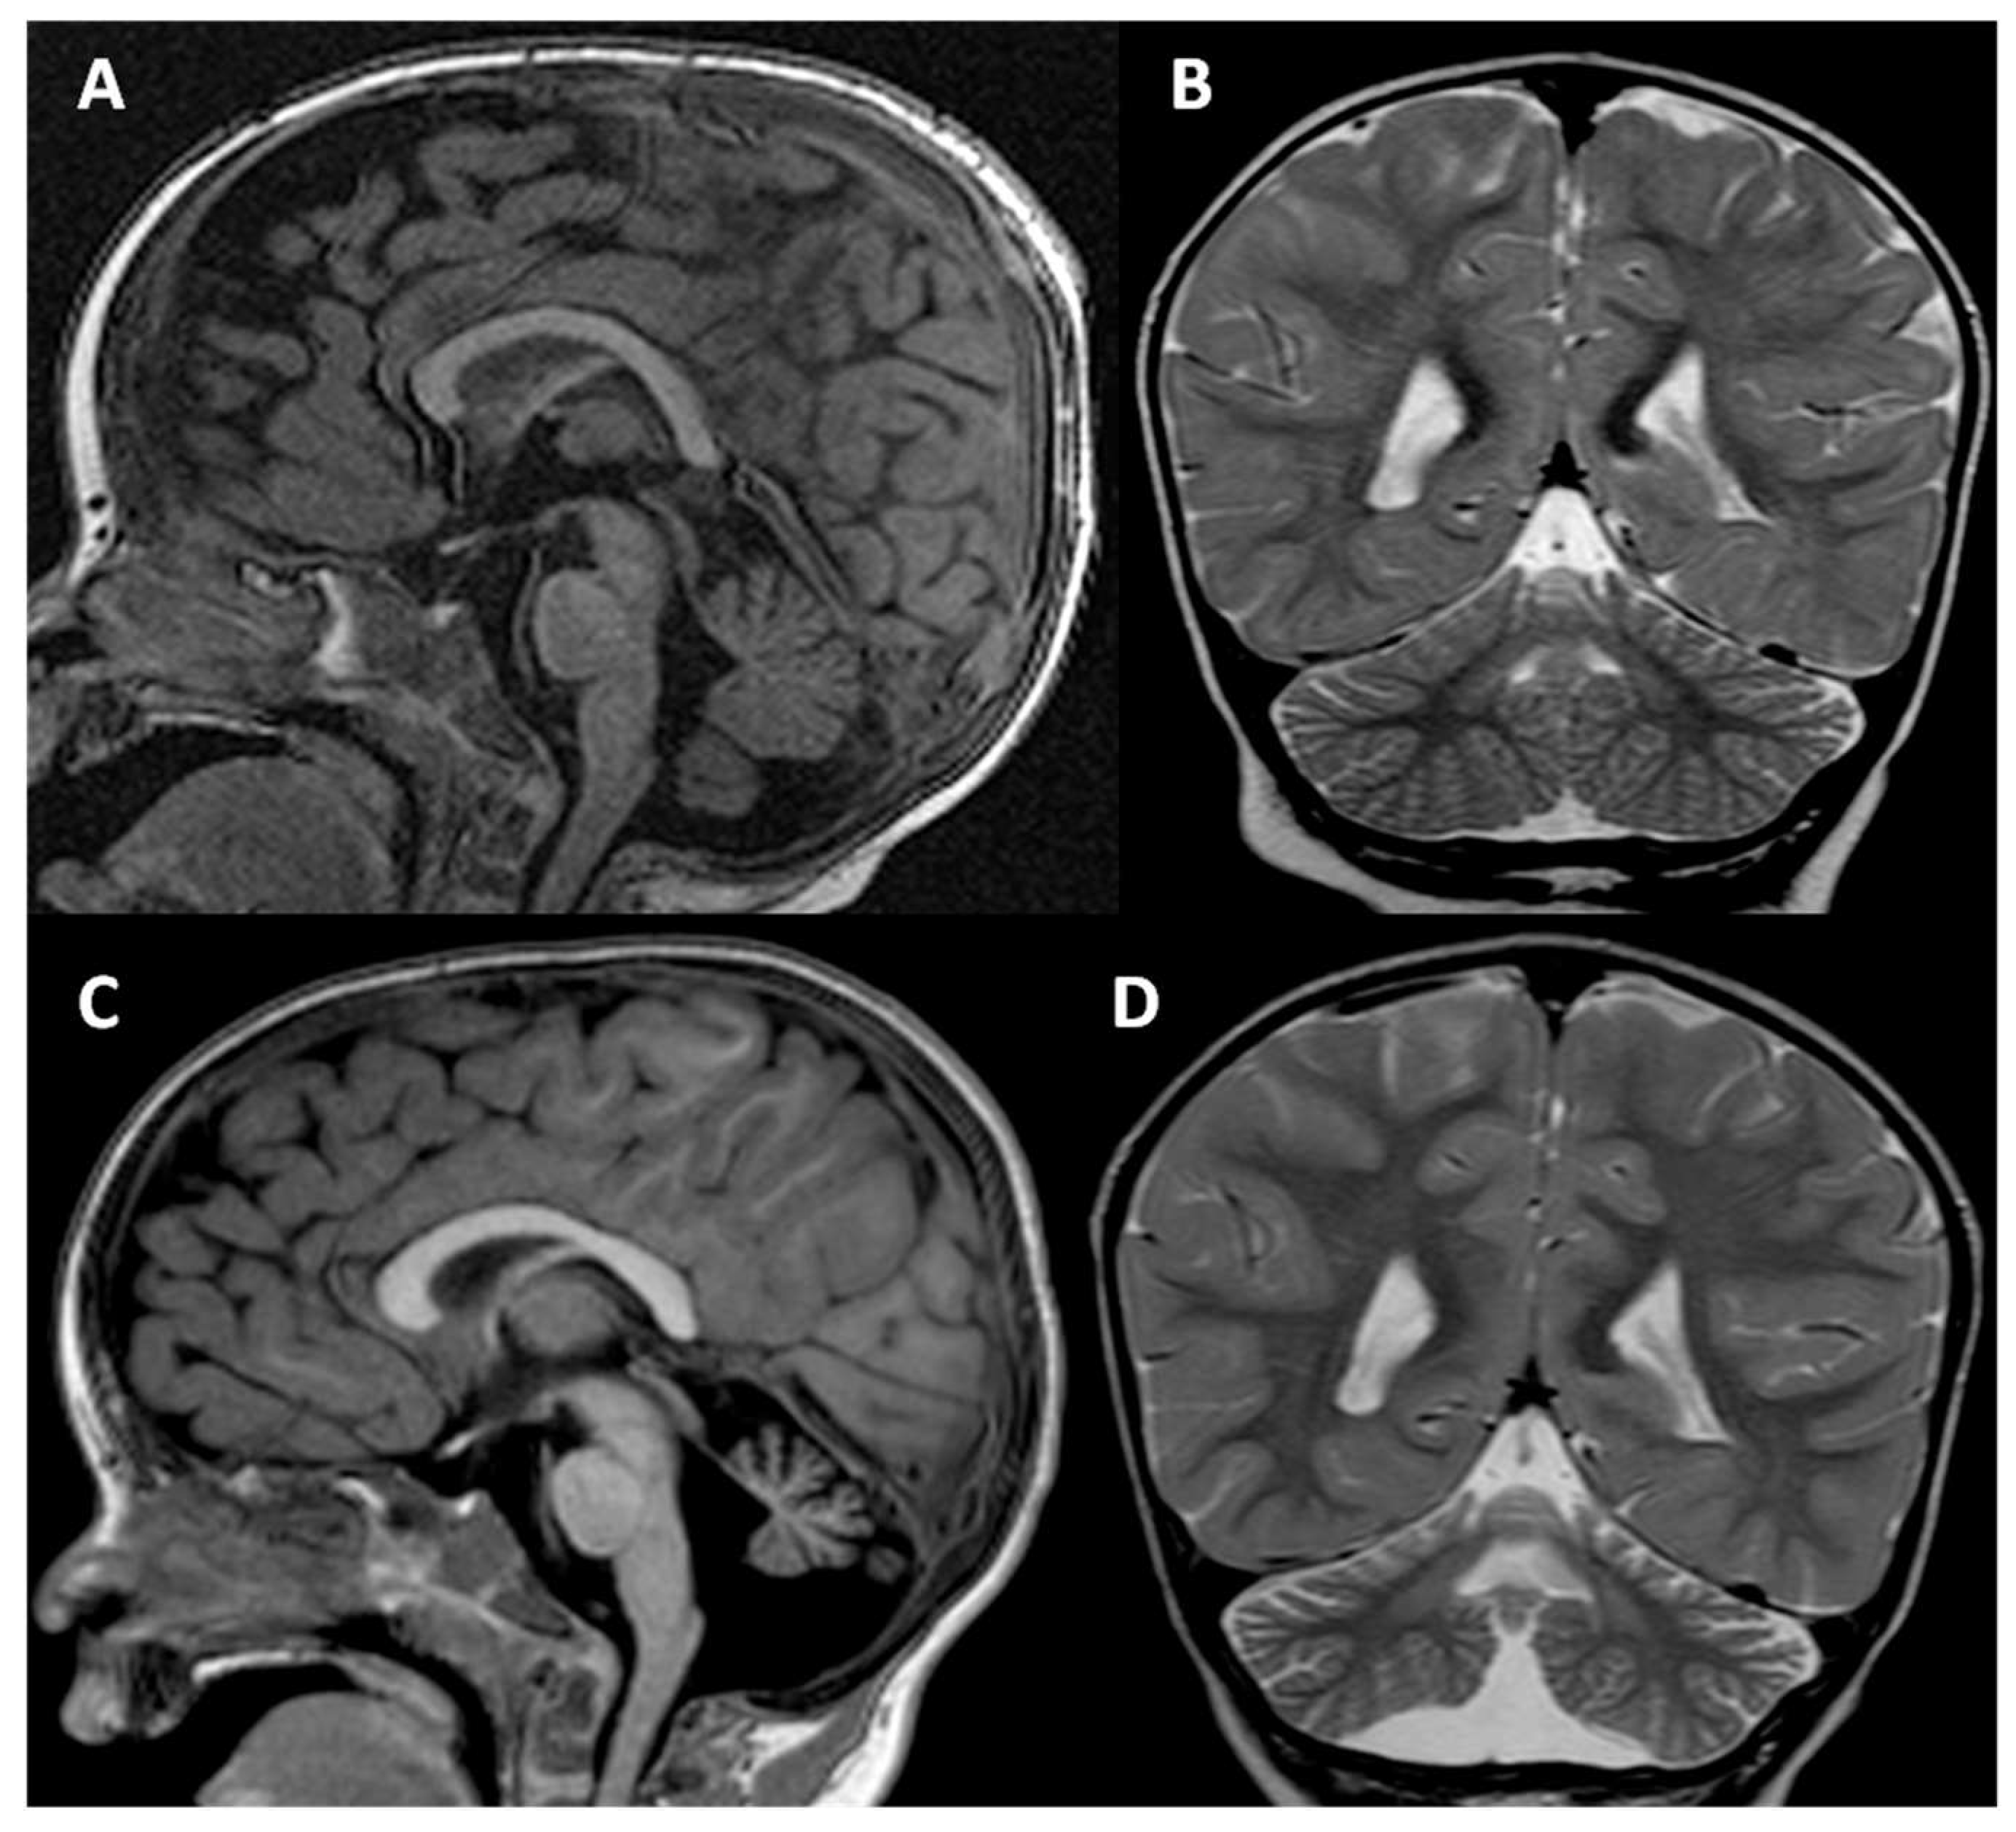

2. Clinical Report

4. Results